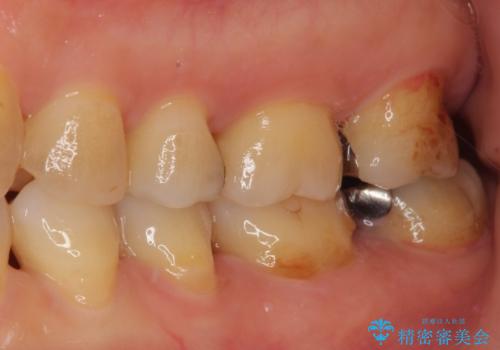

ゴールドは「白い歯」ではありませんが、銀歯の金属色とは異なり、非常にきれいな色合いが特徴です。

もちろん、適合が極めて良いという圧倒的メリットもゴールドクラウンやゴールドインレーの特徴です。